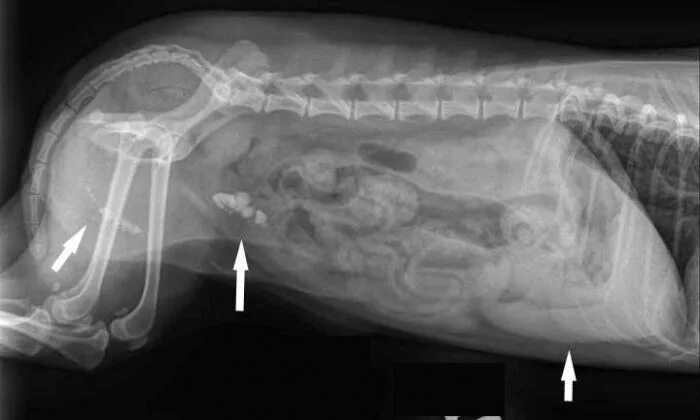

Узи брюшной полости коту